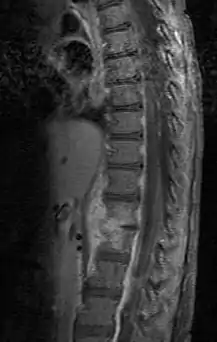

| Discitis in a 2 year old child. | |

Diagnosis is usually apparent on MRI, although plain X-rays and CT examinations can be suggestive. The MRI will reveal air changes in the disc and possibly even external involvement involving the bone or epidural regions. A biopsy may be performed and helps with diagnosis in some cases but often an organism is not obtained. C-reactive protein levels and ESR levels will be elevated and are useful for treatment. Often, the white blood cell count will be normal and the patient will be afebrile.